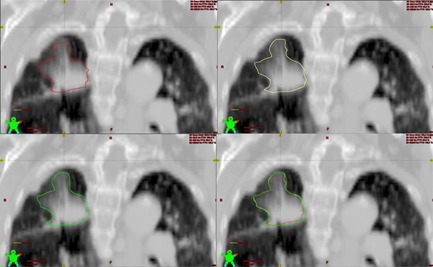

Figure 1.

Example of the ITV combined definition of an early stage non‐small cell lung cancer. The delineations of tumor volume were projected to AIP images. The red line represents GTV 3D, the yellow line represents ITVmip, and green line represents ITVcombined, which is the combination of GTV 3D and ITVmip. We can see from the upper‐left picture that GTV 3D cannot encompass the full range of tumor volume, but ITVmip can cover the tumor volume to a large extent.